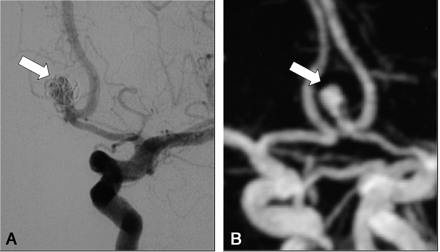

A, DSA of the left internal carotid artery at 9 months after treatment of a 7-mm aneurysm of the anterior communicating artery. The frontal head view shows a large recanalization (arrow) classified as residual aneurysm (class 3).

B, Contrast-enhanced MR angiograph with MIP reconstruction in the frontal plane (arrow) demonstrates a residual aneurysm (class 3) in accordance with DSA findings.